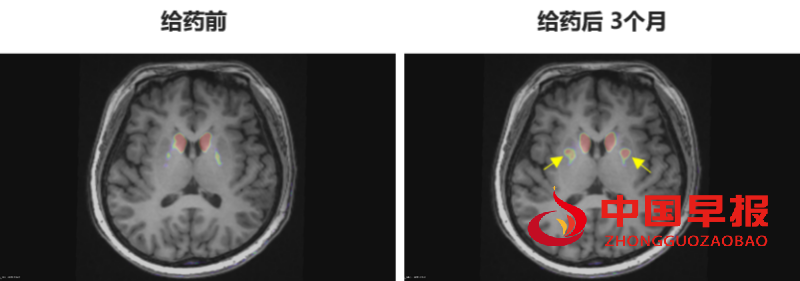

多巴胺能功能成像:神经突触多巴胺能显像是评估人脑黑质纹状体神经元完整性和功能的“金标准”,常用于帕金森病亚临床诊断1-2。接受移植手术3个月后PET-DAT/MRI融合影像明确显示,移植细胞已在患者脑内定植并成功转化为有功能的多巴胺能神经元,双侧纹状体形成显著的de novo新生多巴胺能活性成像(如下图箭头所指), 为功能性治愈提供了最直观的证据。

EOPD患者PET-DAT/MRI融合图像术前与术后三个月对比

注:影像图中黄色箭头指示为NCR201移植后,双侧纹状体出现的新生多巴胺能活性信号,提示移植细胞已定植并高效转化为功能性多巴胺能神经元